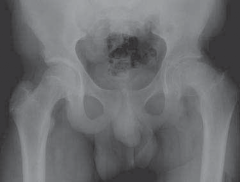

Chapter 75 Bernese Periacetabular Osteotomy Travis H. Matheney and Michael B. Millis DEFINITION Hip dysplasia…

Chapter 80 Flexion Intertrochanteric Osteotomy for Severe Slipped Capital Femoral Epiphysis Young-Jo Kim and …

Chapter 77 Valgus Osteotomy for Developmental Coxa Vara Michael B. Millis and Joshua A. Strassberg DEFINITION…

Chapter 72 Labral Support (Shelf) Procedure for Perthes Disease J. Richard Bowen DEFINITION The labral suppor…

Chapter 78 Valgus Osteotomy for Perthes Disease Ellen M. Raney DEFINITION Valgus osteotomy for Legg-Calvé-Per…

Chapter 79 Percutaneous In Situ Cannulated Screw Fixation of the Slipped Capital Femoral Epiphysis Richard S.…

Chapter 70 Innominate Osteotomy of Salter Richard E. Bowen and Norman Y. Otsuka DEFINITION The Salter innomin…